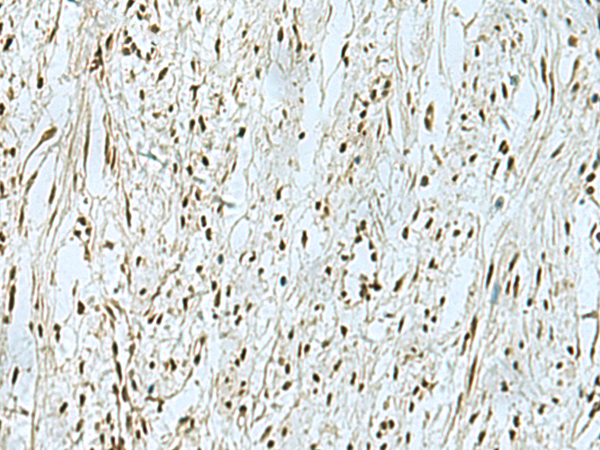

IHC (Immunohistochemistry)

(The image is immunohistochemistry of paraffin-embedded Human ovarian cancer tissue using 47370(THTPA Antibody) at dilution 1/90.(Original magnification: 200))